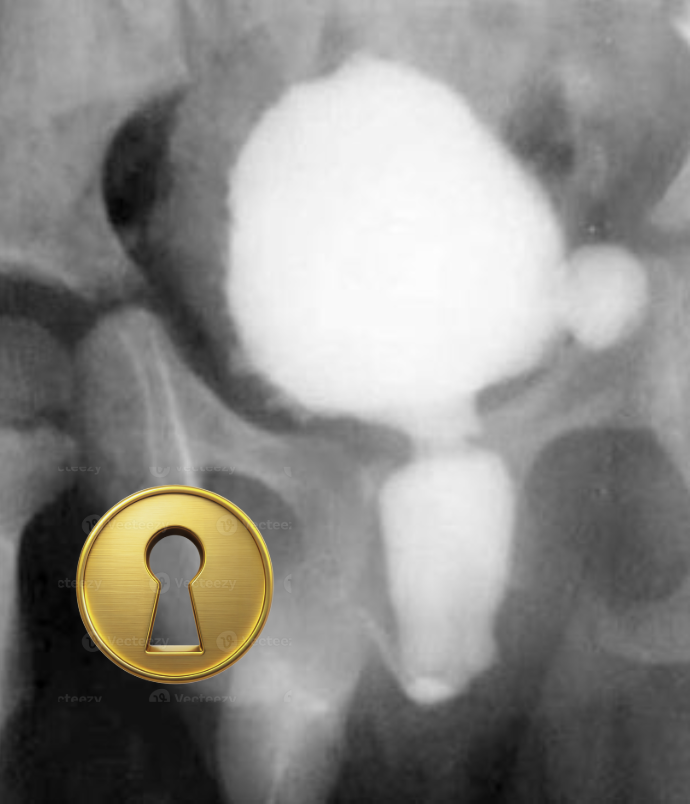

Qual sinal sugestivo de válvula de uretra posterior?

A

Sinal da fechadura